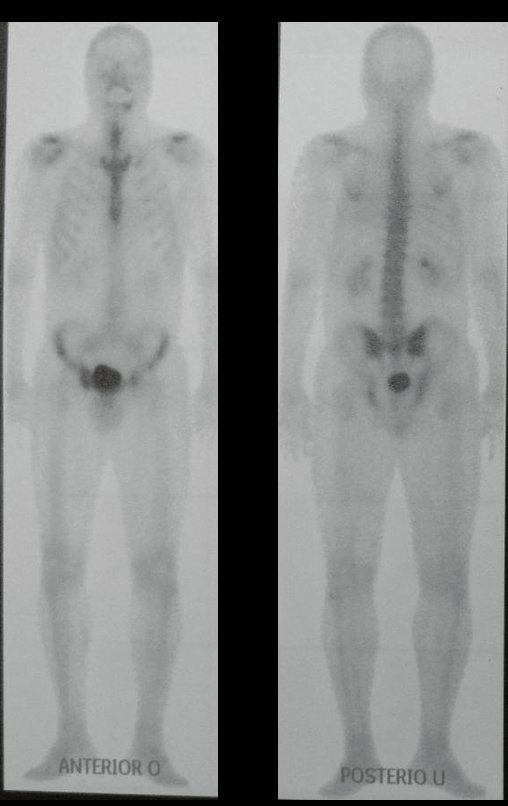

Kidney Cancer Metastasis. Hypernephroma bone metastasis, also known as metastatic kidney cancer to the bone, is a serious complication of kidney cancer. Hypernephroma, or renal cell carcinoma, is a common form of cancer that originates in the kidneys. When bone metastasis occurs, cancer cells spread from the kidneys to the bones, potentially affecting several areas of the skeleton.

This spread of cancer to the bones can cause a series of symptoms, such as persistent bone pain, pathological fractures and impaired mobility. Furthermore, bone metastasis from hypernephroma can lead to serious complications such as spinal cord compression that require immediate medical intervention.